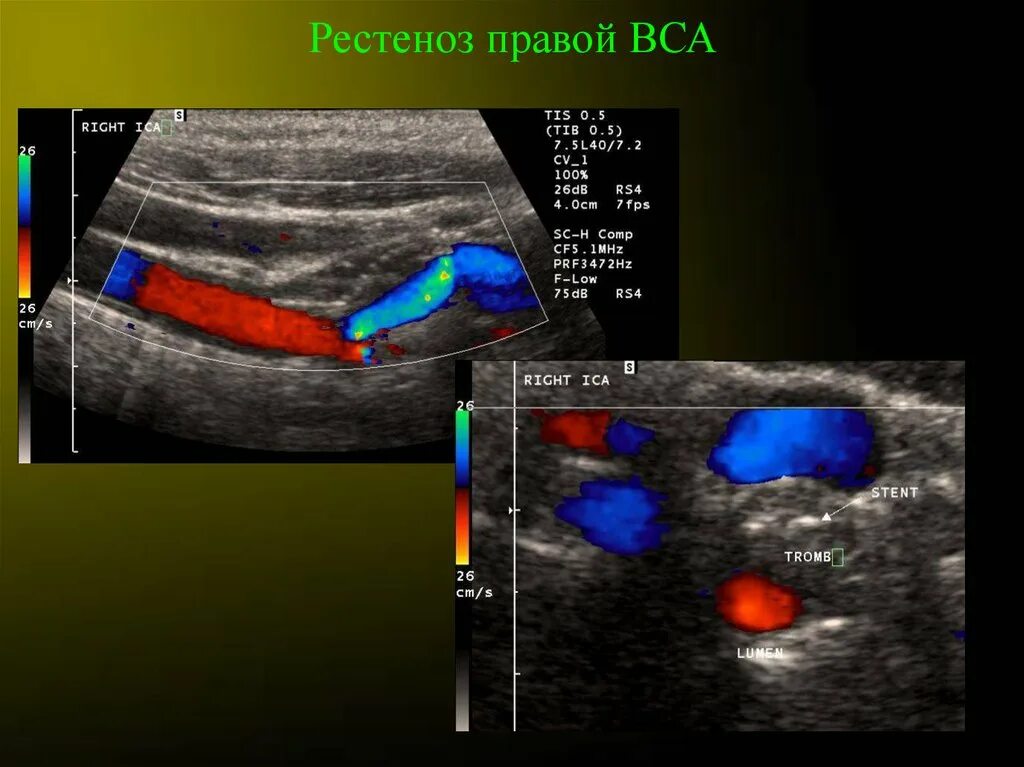

1.4 вса